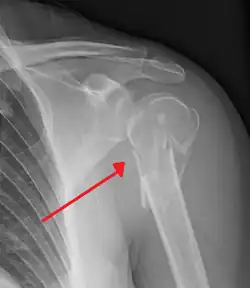

Fracture of the proximal humerus -

Surgical neck

The surgical neck is a narrow area distal to the tubercles that is a common site of fracture. It makes contact with the axillary nerve and the posterior humeral circumflex artery.

The head (caput humeri) is nearly hemispherical in form. It is directed upward, medialward, and a little backward, and articulates with the glenoid cavity of the scapula to form the glenohumeral joint (shoulder joint). The circumference of its articular surface is slightly constricted and is termed the anatomical neck, in contradistinction to a constriction below the tubercles called the surgical neck which is frequently the seat of fracture. Fracture of the anatomical neck rarely occurs.[2] The diameter of the humeral head is generally larger in men than in women.

The humerus (/ˈhjuːmərəs/; pl.: humeri) is a long bone in the arm that runs from the shoulder to the elbow. It connects the scapula and the two bones of the lower arm, the radius and ulna, and consists of three sections. The humeral upper extremity consists of a rounded head, a narrow neck, and two short processes (tubercles, sometimes called tuberosities). The shaft is cylindrical in its upper portion, and more prismatic below. The lower extremity consists of 2 epicondyles, 2 processes (trochlea and capitulum), and 3 fossae (radial fossa, coronoid fossa, and olecranon fossa). As well as its true anatomical neck, the constriction below the greater and lesser tubercles of the humerus is referred to as its surgical neck due to its tendency to fracture, thus often becoming the focus of surgeons.